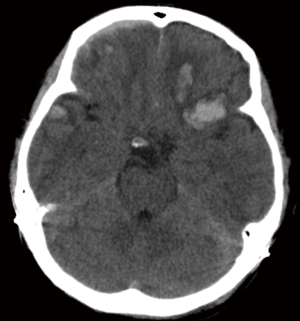

Acute SDHs

For patients presenting with an acute SDH the generally accepted indications for surgery is a thickness greater than 10 mm and midline shift greater than 5 mm on the CT scan (Figure 2). It is recommended that patients presenting with these findings be operated on regardless of their GCS. Furthermore, patients with a GCS less than 9 an acute SDH can warrant some form of ICP monitoring. This is due to the higher likelihood of underlying cerebral injury, parenchymal contusions, deep shear injury, or cortical injury, which relate to the mechanism of injury. Recommendations do not distinguish between intraparenchymal monitors, EVDs or Licox. Observation, medical management and repeat CTs are acceptable with an acute SDH less than 10 mm thickness or less than 5 mm of midline shift. However, should the GCS fall by 2 or more points from injury to presentation, the ICP rise to greater than 20 mmHg or if abnormal pupillary responses are observed, surgery is recommended. If the decision to proceed to surgery is made, the timing should be emergent. The preferred method is a craniotomy with or without bone flap removal or duraplasty depending on intraoperative findings (39). There is controversy with regards to performing a craniotomy or a craniectomy in the setting of acute SDH (40).